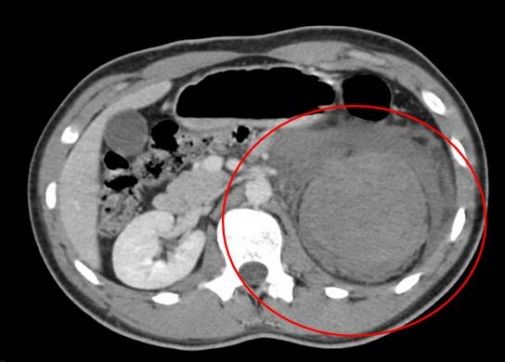

CT scan van de buik met een nierletsel

Als een patiënt een ‘hoog-energetisch ongeval’ heeft doorgemaakt, dan komt de patiënt vrijwel altijd met de ambulance of helikopter in het ziekenhuis. Op de Spoedeisende hulp wordt de patiënt dan via een vast stramien opgevangen, waarbij er volgens een ABCD principe naar de patiënt gekeken wordt, waarbij de A staat voor ‘airway’ (of de luchtwegen nog goed zijn) de B voor ‘breathing’ (of de ademhalingsorganen nog goed werken) de C voor ‘circulation’ (of de bloedsomloop nog goed werkt) en de D voor ‘disability’ (of er neurologische uitval is) Er zullen al snel Rontgen foto’s van de patiënt worden gemaakt en een echografie van de buik. Vaak zijn er op de echografie van de buik al tekenen van inwendige schade (zoals bijvoorbeeld vrij bloed in de buikholte). In veel ziekenhuizen zal er vervolgens een CT-scan van de buik worden gemaakt, om letsels aan de inwendige buikorganen aan te tonen, danwel uit te sluiten.